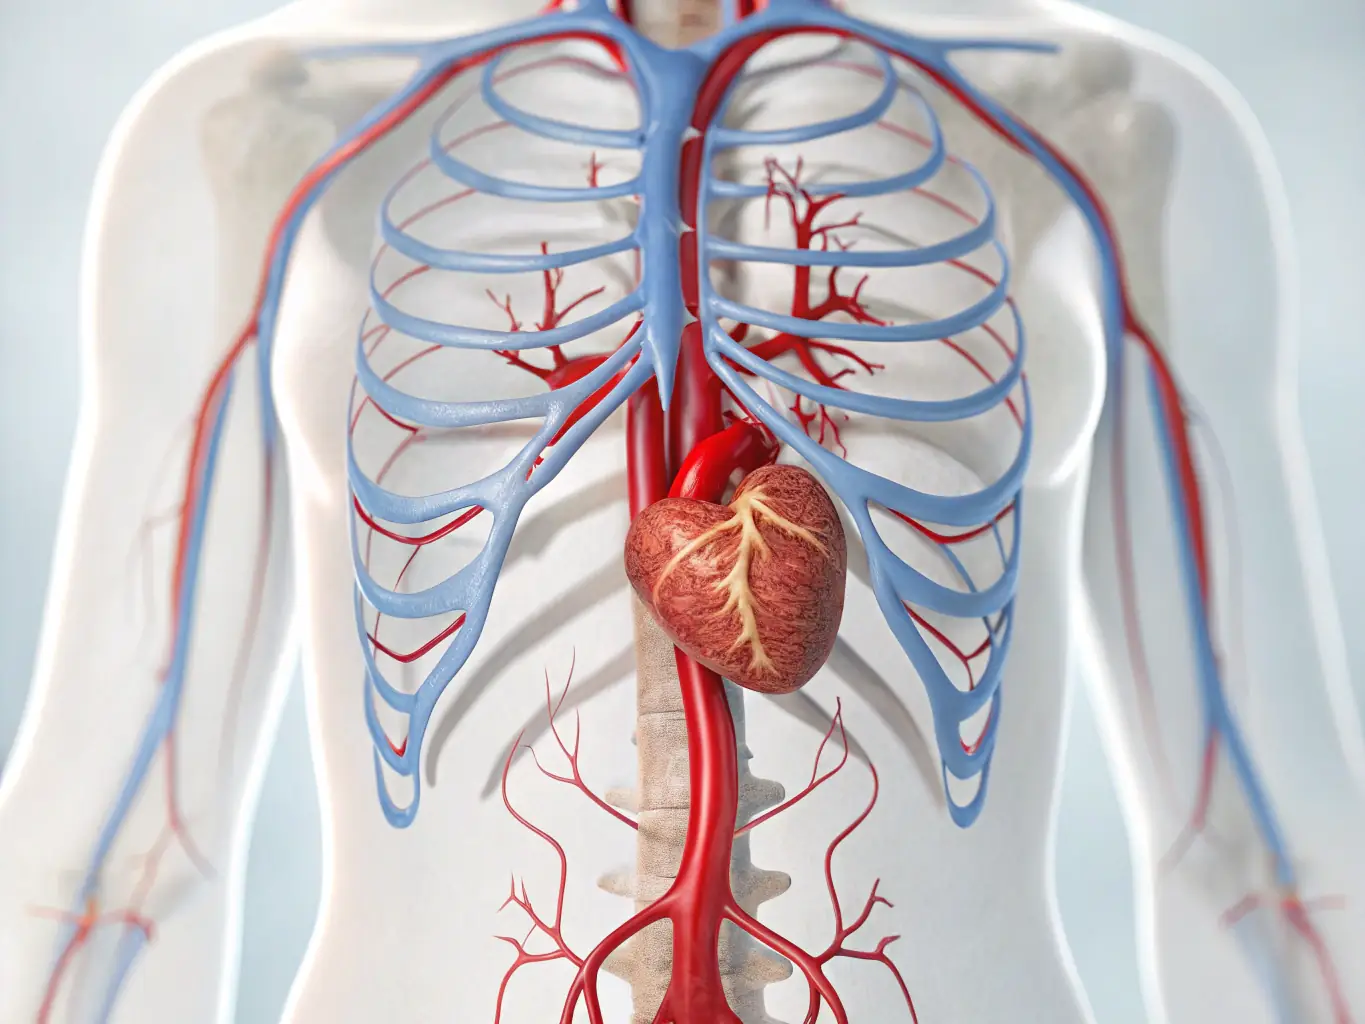

At Murrieta Valley Surgery Associates, our vascular surgeons provide comprehensive care for a range of conditions, including PAD, varicose veins, and aneurysmal disease. We are committed to improving your vascular health.

At Murrieta Valley Surgery Associates, we are dedicated to providing state-of-the-art vascular care. Our experienced team utilizes advanced techniques to treat a wide range of conditions, ensuring the best possible outcomes for our patients. We are committed to staying at the forefront of vascular surgery, offering innovative solutions for complex problems.

Endovascular Interventions

Varicose Vein Treatments

Hemodialysis Access

Temporal (Giant Cell) Arteritis

Vascular Ultrasound